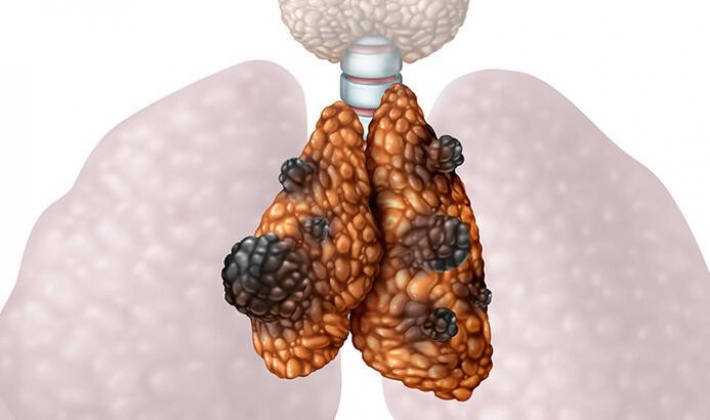

Göğüs Cerrahisi Uzmanı Doç.Dr. Özkan Demirhan,"Timus bezinden kaynaklı bir tümör olan timoma genellikle timus bezinden kaynaklanarak etrafına doğru, yavaş büyüyen ve nadir görülen bir kanser türüdür. Timus bezi ergenlik dönemine kadar bağışıklık sisteminin önemli bir parçası olan T lenfositlerinin yapım yeridir ve gelişmesini sağlar. Ergenliğe doğru küçülmeye başlar ve zamanla işlevini kaybeder” dedi.

Timomanın belirtilerine değinen Özkan Demirhan,"Timomalar çoğu zaman belirti vermez ancak büyümeye başlayınca öksürük, göğüs ağrısı, ses kısıklığı, yutma güçlüğü, nefes darlığı, iştahsızlık gibi belirtiler verirler. Nadir durumlarda deri döküntüsü ve kansızlık gibi belirtiler de görülebilir. Bazı durumlarda yine nadiren vena kavaya (SVC) yani kol ve kafanın toplardamarlarının birleşerek kalbe döküldüğü damara baskı yaparak Superior Vena Cava Sendromu' na (SVCS) neden olabilir. SVCS durumunda boyun, göğüs ve yüzde şişlik oluşur ve vücudun üst tarafındaki görünür damarlar şişer. Bu tabloya baş ağrısı ve baş dönmesi gibi belirtiler de eşlik eder.

Bağışıklık sisteminin kendi kendine saldırması sonucu oluşan miyasteni gravis, kırmızı hücre aplazisi, hipogamaglobulinemi, lupus, polimiyozit, ülseratif kolit, romatoid artrit, Sjogren Sendromu, sarkoidoz ve skleroderma gibi bağışıklık sistemi hastalıkları da timoma bağlantılı olabilir" şeklinde bilgi verdi.

Timomanın teşhis yöntemlerine ve tedavi seçeneklerine de değinen Demirhan, "Timoma genelde başka nedenlerle tarama veya kontrol yapıldığı zaman tesadüfen tespit edilir. Timomanın tanısı ve evrelemesi için Bilgisayarlı Tomografi (BT), Magnetik Rezonans( MR) ve PET CT ile hastalığın kapsamı, tümörün yakındaki dokulara yayılım durumu, hücre tipi dikkate alınır. Tanı için ileri evre tümörlerde mutlaka hücre tipi tayini yapılmalıdır. Bazen timoma dışı bir hastalıkla ile karıştırılabilir. Biyopsi için ve kesin tanı için mutlaka yeterli materyal alınmalıdır” ifadelerini kullandı.

Timomanın tedavi seçeneklerine değinen Dr. Demirhan, "Timomada tedavi seçenekleri hastalığın evrelerine göre belirlenir. Timomanın 4 evresi vardır. Evre 1’de tümör bir kapsül içerisinde sınırlıdır. Evre 2’de tümör kapsülünü invaze eder. Evre 3’te timoma kapsülü aşarak nefes borusu, akciğer, damarlar, kalp zarına uzanır. Evre 4’te timoma uzak organlara yayılım gösterir. 1’inci ve 2’inci evre timomalar cerrahi yöntemler ile çıkarılır ve ardından hastaya onkolojik işlemler olan kemoterapi ya da radyoterapiye genelde gerek duyulmaz. 3’üncü evre timomalar genellikle çevre dokulara yayılım yapmış tümörler oldukları için önce kemoterapi ve radyoterapi ile tümörün çevre dokulardaki yayılımı geriletilir, ardından da tümör cerrahi tedavi ile çıkarılır. Ameliyat sonrası onkolojik işlemler uygulanmaya devam edilir. 4’üncü evre timomalarda çevre organlara yayılım olduğu için cerrahiye uygun değildir ve sadece onkolojik işlemler uygulanır. Diğer kanser türlerinde olduğu gibi timomanın da erken evrede tespit edilmesi önemlidir ve erken evre hastalıklarda birincil tedavisi cerrahidir" bilgilerini paylaştı.